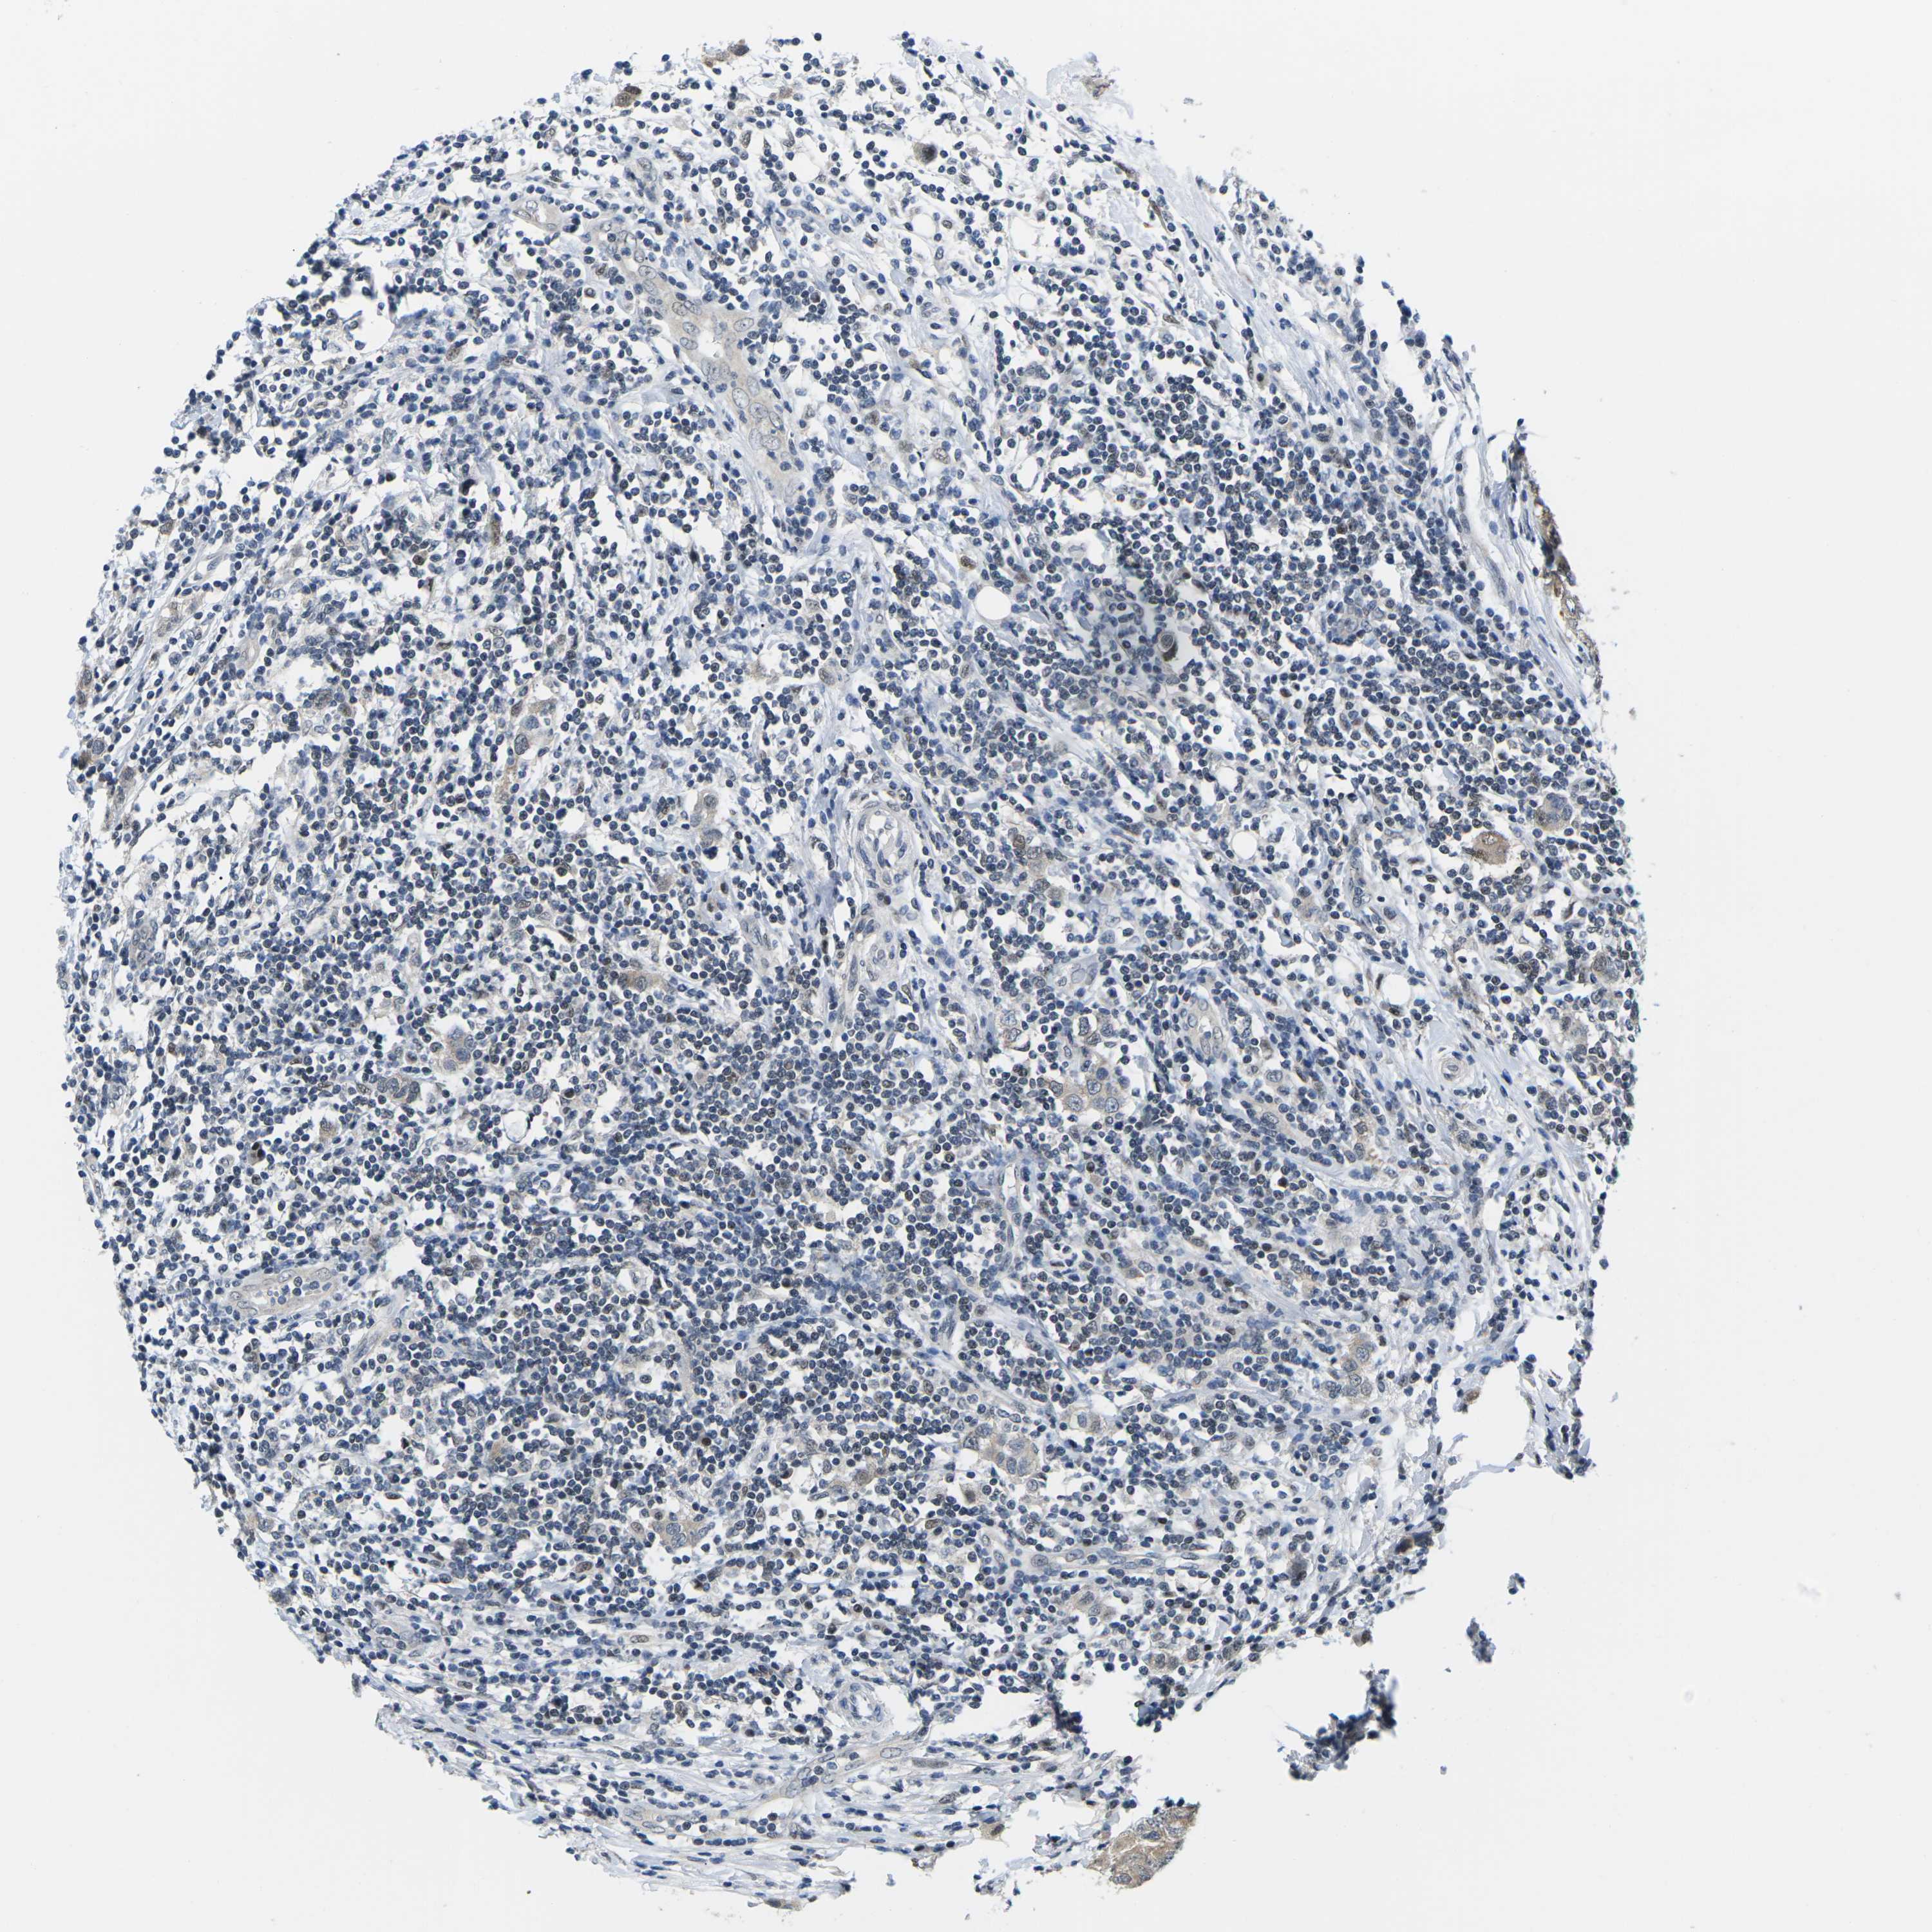

CANCER BREAST CANCER Show tissue menu

BRCA TCGA BRCA VALIDATION PROTEIN EXPRESSION